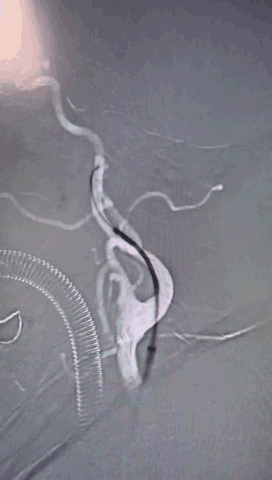

右侧股动脉穿刺,置8F鞘管,泥鳅导丝携6F 90cm Locaste输送导管内衬125cm多功能单弯导管超选至左侧颈内动脉C1段,6F 115cm Skathi远端通路导管到达C4段。

依据动脉瘤3D,调整机架位置使得动脉瘤及载瘤动脉显影最佳,Echelon-10微导管塑形理想,顺利超选至瘤内,先尝试单纯弹簧圈栓塞,必要时再采用支架辅助。

按大小顺序依次填塞弹簧圈(Jasper SS 3*8 Axium Prine 2*4、1*3)且弹簧圈成篮稳定,最终达到致密栓塞效果,手术过程顺利。